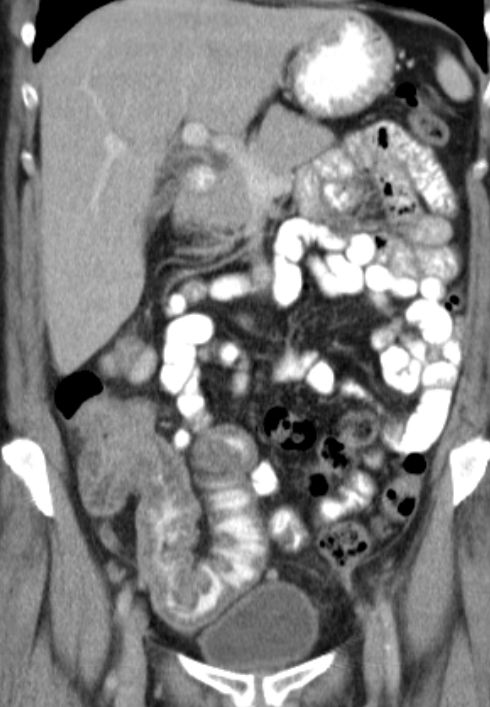

| Colon ascendens | 73-jähriger Mann mit einer Stenosesymptomatik.

Das CT zeigt einen Tumor des Colon ascendens.

Zusätzlich peritoneale und mesenteriale Metastasierung. |